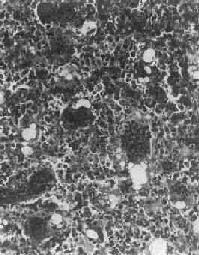

图17-3 骨软骨瘤 图示特征性的三层结构,即最表浅的纤维层,中间的软骨层(软骨帽)和深部的松质骨 【临床病理联系】 骨软骨瘤一般无明显症状,只是局部肿块形成。有时肿块压迫周围组织,引起疼痛和不适。如果肿块体积迅速增大,软骨帽增厚至1cm以上,则须考虑恶变的可能,这在多发性者比单发性者多见。本瘤如手术切除不彻底,则易复发,多发生在1年或数年后。 (二)软骨肉瘤 软骨肉瘤(chondrosarcoma)是从软骨细胞发生的原发性恶性骨肿瘤,由肿瘤性软骨细胞及软骨基质组成。软骨肉瘤是颇为常见的恶性骨肿瘤,其发病率仅次于骨肉瘤,其发病年龄多在中年以后,多见于40~70岁,根据发病部位不同,可分为中央型及周围型两种。中央型从骨髓腔发生,肿瘤为骨皮质所包绕或穿破骨皮质,多见于长管状骨,特别是股骨和胫骨;周围型从骨肿瘤表层出发,向周围软组织及骨皮质侵犯,多见于骨盆、肩胛骨及肋骨等。少数软骨肉瘤来自软骨瘤和骨软骨瘤之恶变。 【病理变化】 肉眼观,中央型软骨肉瘤主要发生在骨髓腔内,呈灰白色、半透明的分叶状肿物,其中常见淡黄色的钙化或骨化小灶。这些钙化或骨化小灶在X线片上可以看到,对诊断软骨肉瘤很有帮助,但高度恶性的软骨肉瘤钙化常不明显。随肿瘤的增大可使骨髓腔变大并侵犯骨皮质,骨外膜受刺激后,可有反应性新骨形成,使受累骨皮质增厚。恶性程度较高的软骨肉瘤,在早期即可穿破骨皮质,向软组织内扩展,形成较大的肿块,周围没有新骨形成。外围型软骨肉瘤瘤体主要在骨外,其表面被覆一层薄而不完整的包膜。以上两型软骨肉瘤均常发生粘液变、出血及囊性变等继发性变化。 镜下观,肿瘤的分化程度差异很大,分化好的软骨肉瘤在镜下易误诊为软骨瘤,但在肿瘤的边缘可以找到瘤细胞的异型性,如核肥大、深染,出现较多的双核、巨核和多核瘤巨细胞,并可见明显核仁(图17-4)。在分化差的软骨肉瘤则上述瘤细胞的异型性很明显,核分裂像也多见。软骨肉瘤的基质可为与一般透明软骨相似的透明基质,也可为粘液样基质,常见于恶性程度高的软骨肉瘤。

图17-4 软骨肉瘤 软骨细胞大小不等,有的较大。许多细胞有肥硕的胞核,有的有双核 【临床病理联系】 局部疼痛及肿块往往是软骨肉瘤的主要症状。近关节的肿瘤常影响关节活动。盆骨的巨大软骨肉瘤可压迫邻近器官,引起相应症状。软骨肉瘤的分化程度对临床经过有一定影响,分化较好的软骨肉瘤往往生长较慢,预后较好。软骨肉瘤一般比骨肉瘤生长慢,转移也较晚。血道转移可至肺、肝、肾及脑等处,淋巴结转移极罕见。软骨肉瘤术后常易复发,多次复发常使恶性程度增加。 (三)骨巨细胞瘤 骨巨细胞瘤(giant cell tumor of bone)是一种具有局部侵袭性及复发倾向的原发性骨肿瘤。由梭形和卵圆形的基质细胞(stromal cell)及大量散布在其间的多核巨细胞组成,肿瘤间质富于血管。由于本瘤内有大量多核巨细胞,因而称为巨细胞瘤;又因过去认为这些多核巨细胞是破骨细胞,故也称为破骨细胞瘤(osteoclastoma)。本瘤的组织来源未明,以上各名称纯系形态学的描述性命名。在我国骨巨细胞瘤的发病率较高,仅次于骨软骨瘤和骨肉瘤,居第三位。本瘤好发年龄为20~40岁的青壮年,性别无明显差异。 【病理变化】 骨巨细胞瘤多发生于四肢长骨的骨骺端,尤以股骨下端及胫骨上端为多见,约占半数左右,其次为桡骨下端、尺骨下端或肱骨上端等部位。长骨以外则以脊椎为多见。 肉眼观,本瘤常侵犯骨骺线已闭合的长骨端,大多数位于骨骺,早期常为偏心性生长,增大的肿瘤使骨皮质受累而向外膨胀。在肿瘤周围往往有菲薄的骨壳,乃由骨内、外膜反应性新生骨构成,肿瘤的境界比较清楚。肿瘤内原有松质骨大部分或全部消失,瘤内常有纤维组织或骨性间隔。由于肿瘤组织的溶骨性破坏,常造成病理性骨折(图17-5)。肿瘤组织呈灰红色,质软而脆,较大的肿瘤常合并出血及坏死,并伴有囊性变而形成大小不等的空腔,囊腔内含有浆液性或血性液体。晚期病例骨性包壳如果被破坏,则可侵犯软组织形成肿块。关节软骨有抗肿瘤浸润的作用,关节软骨下骨间质可完全被破坏,致使关节软骨失去支持而扭曲变形。